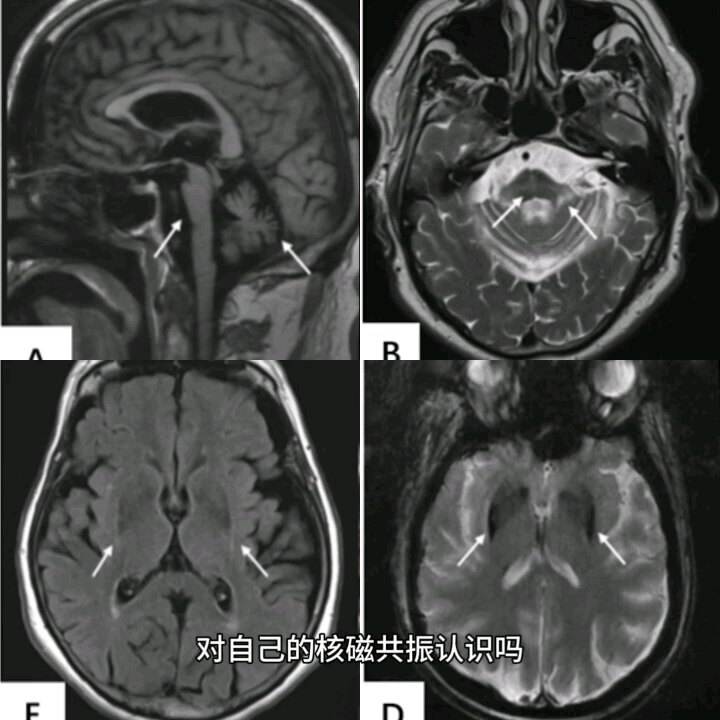

多系統(tǒng)萎縮的核磁共振你認(rèn)識(shí)嗎?